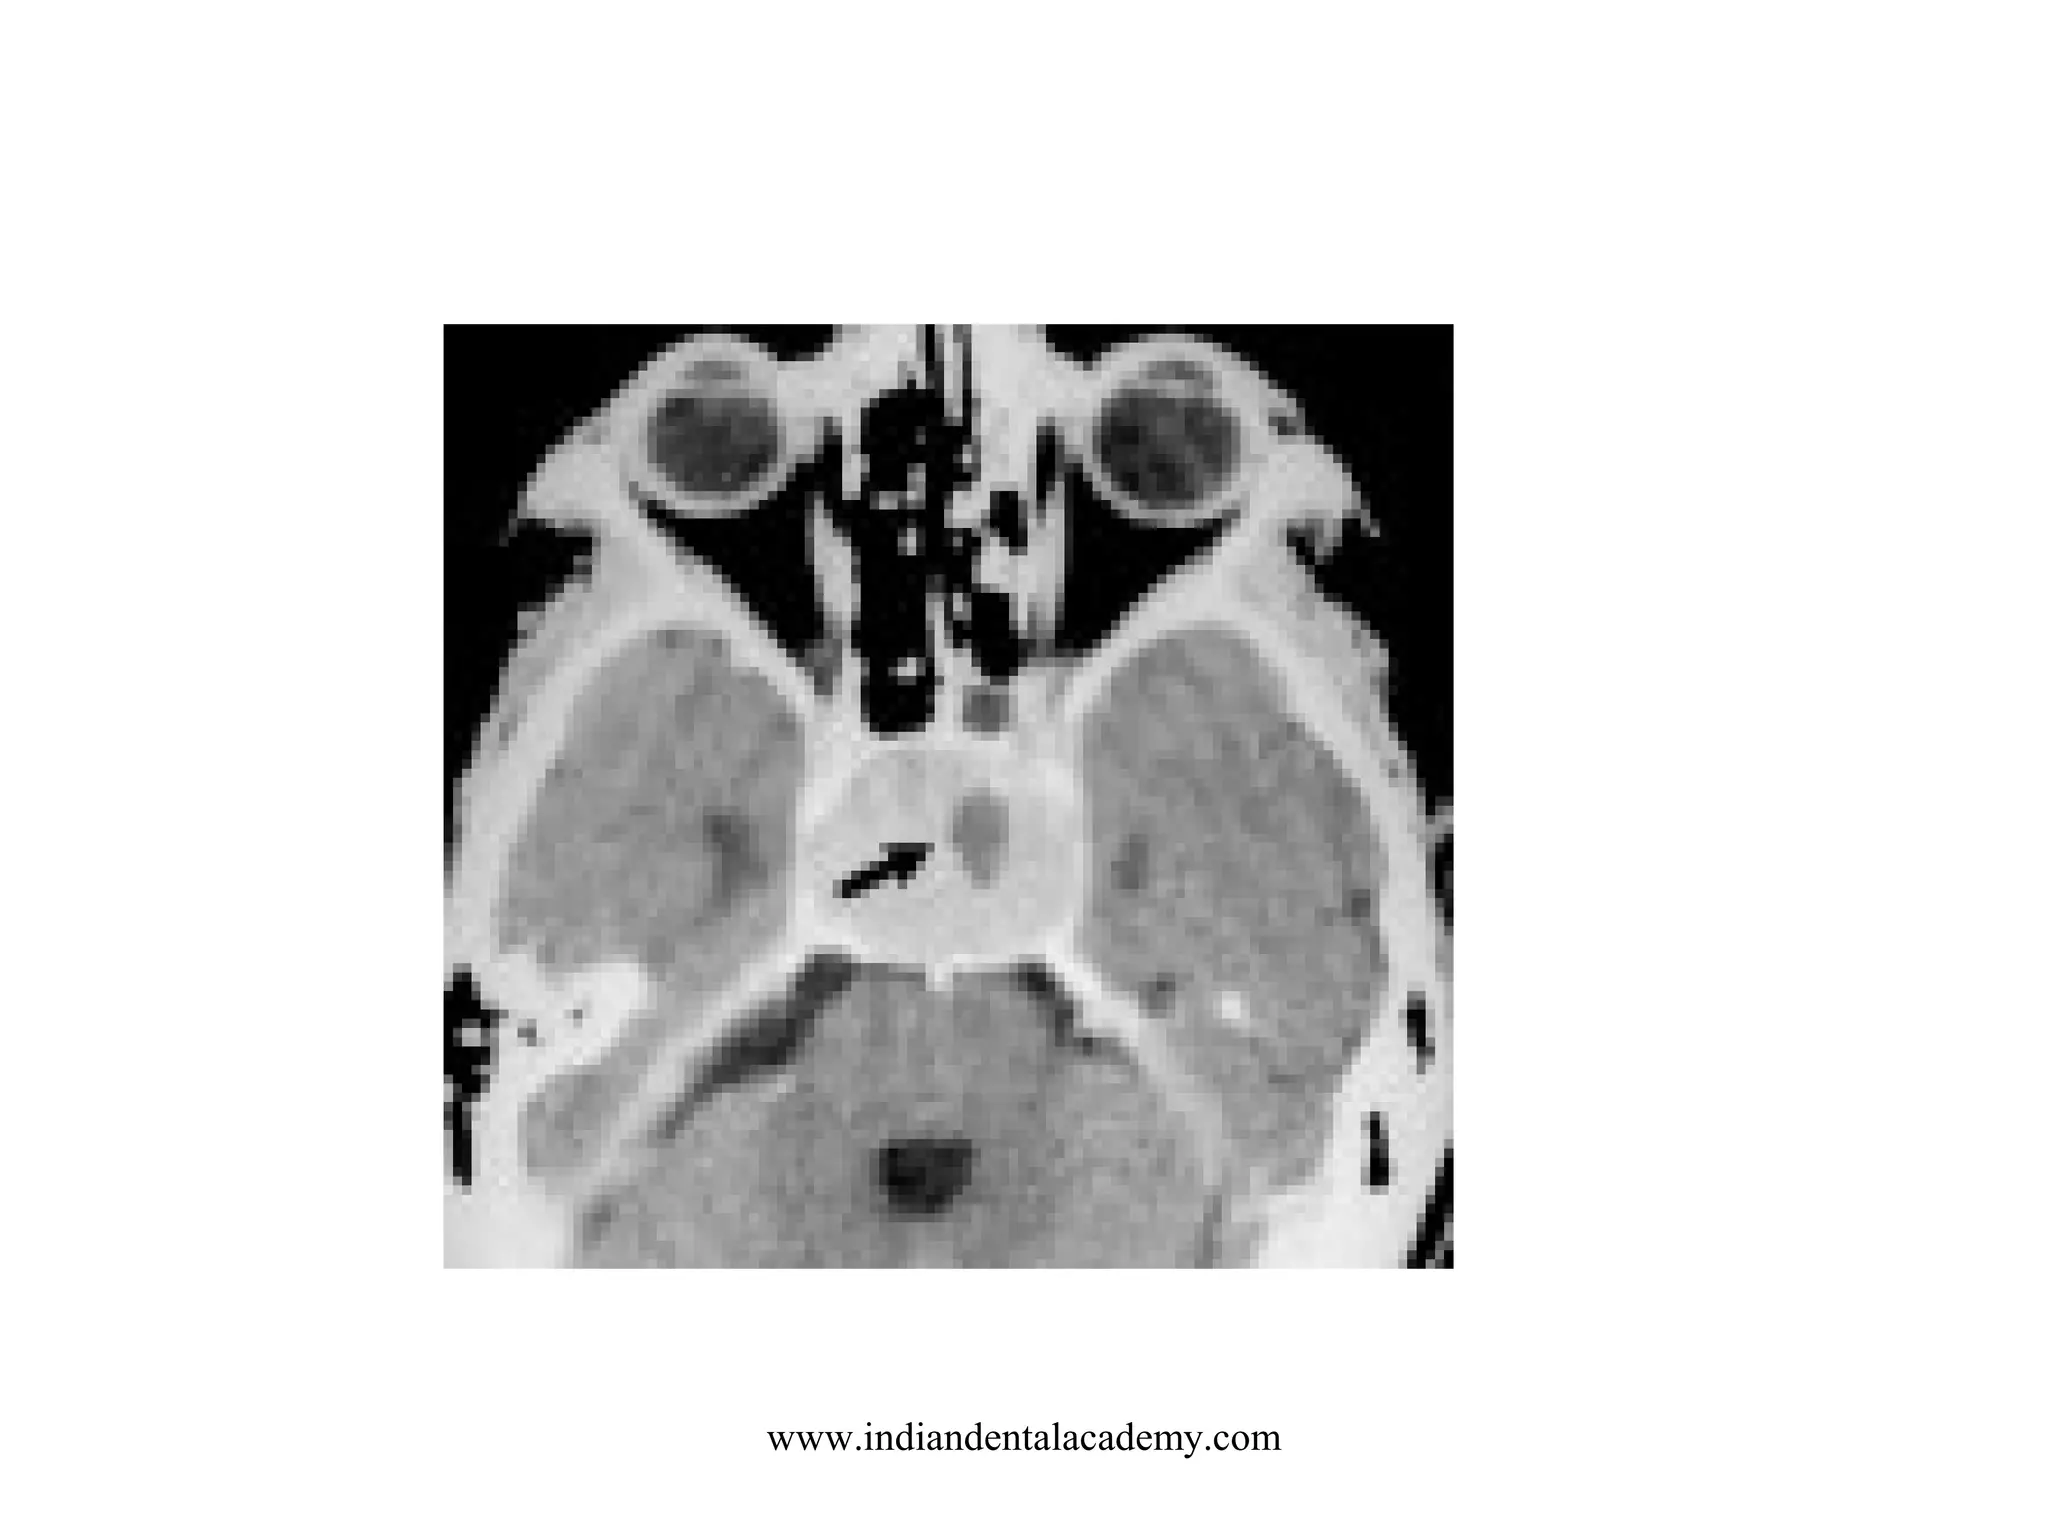

ACOUSTIC NEUROMA

www.indiandentalacademy.com